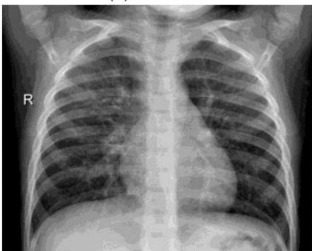

What pathology is seen on this x-ray?

RSV

What is the radiograph appearance of RSV?

Hyper inflated lungs with diffuse interstitial markings. More severe cases – focal areas of atelectasis are present.